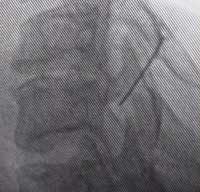

Als weitere Behandlungsmöglichkeit der zervikalen Diskushernie kann man gezielt mit einer dünnen Nadel an die Nervenwurzel gehen, diese mit einem Kontrastmittel darstellen und dann das Medikament, in der Regel Cortison injizieren. |

Bringt auch der Nervenwurzelblock keine Linderung, so muss manchmal operiert werden. Diese Operation wird in der Regel von vorne durchgeführt. Der prolabierte oder ausgetretene Teil der Zwischenwirbelscheibe wird dann herausgenommen und meistens im HWS-Bereich, im Gegensatz zur Lendenwirbelsäule, werden dann die zwei benachbarten Wirbel miteinander verbunden oder verblockt. Eine solche Fusion wird in der Beweglichkeit der HWS kaum wahrgenommen. |